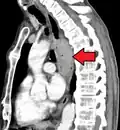

Esophageal cancer (lower part) as a result of Barrettʼs esophagus